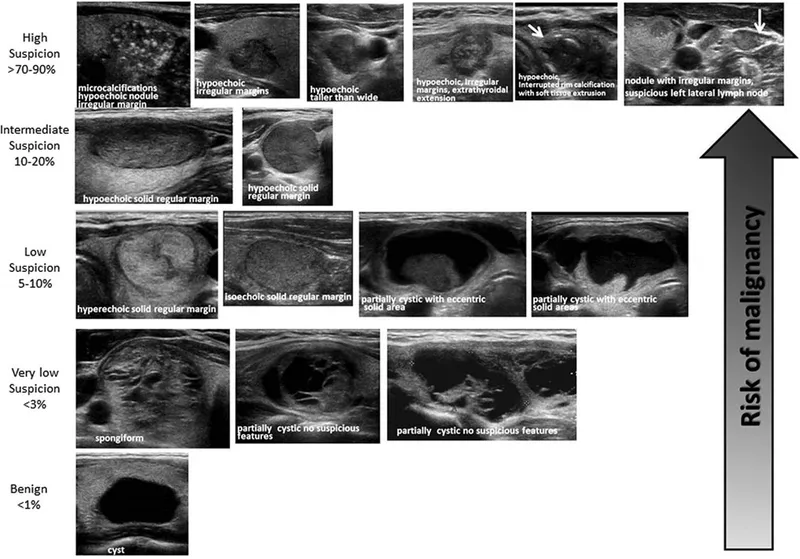

Thyroid USG: Risk stratifies nodules. High-risk features: microcalcifications, marked hypoechogenicity, irregular margins, taller-than-wide, extrathyroidal extension, suspicious nodes. ACR TI-RADS (TR1-TR5) score guides FNAC.

- Indicated for suspicious nodules (e.g., TI-RADS ≥TR3 or high-risk USG features).